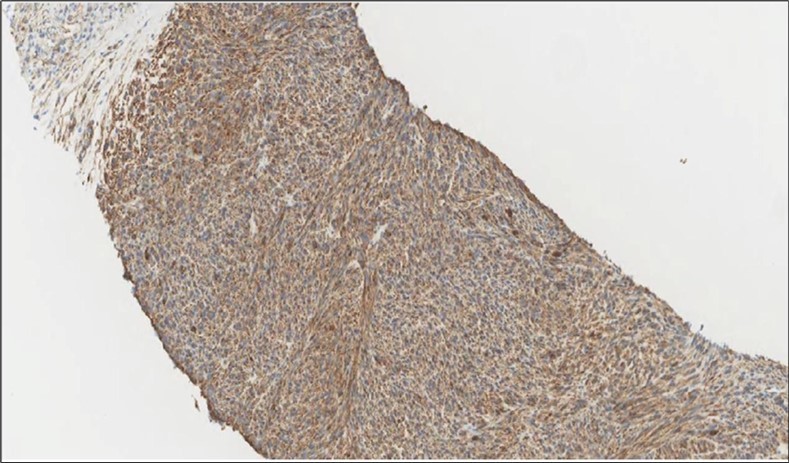

Figure 4.Left thyroid Cells are diffusely positive for Caldesmon immunohistochemistry (IHC, x200)

cancer, or other metastatic tumors without further testing with genetic or molecular studies 3, 7. Immunohistochemical testing plays a vital role in differentiating LMS from such similar tumors as it stains positive for vimentin and smooth muscle actin (SMA), and is variably positive for HHF35, desmin (50%-100%), and H-caldesmon 3, 6. Moreover, there were no reported cases where thyroid LMS stained positive for thyroglobulin, cytokeratin, calcitonin, chromogranin, or protein S100 3. Our patient’s left thyroid biopsy showed the characteristic microscopic features and was positive for SMA, desmin, caldesmon, P63 with patchy EMA (Figure 1, Figure 2, Figure 3, Figure 4) as well as her liver biopsy (Figure 5, Figure 6, Figure 7); whereas her right thyroid showed clear papillary thyroid cancer cell features (Figure 8, Figure 9).